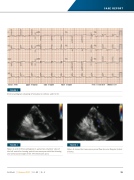

FIGURE 2

Electrocardiogram showing ST elevation in inferior and V3- V6.

FIGURE 3

Figure 3 and 4: Echocardiogram in apical two-chamber view of the left ventricle showing apical true aneurysm with the thinning and aneurysmal bulge of the left ventricular apex.

FIGURE 4

Figure 4 shows the trans-aneurysmal flow by color Doppler (black arrows).